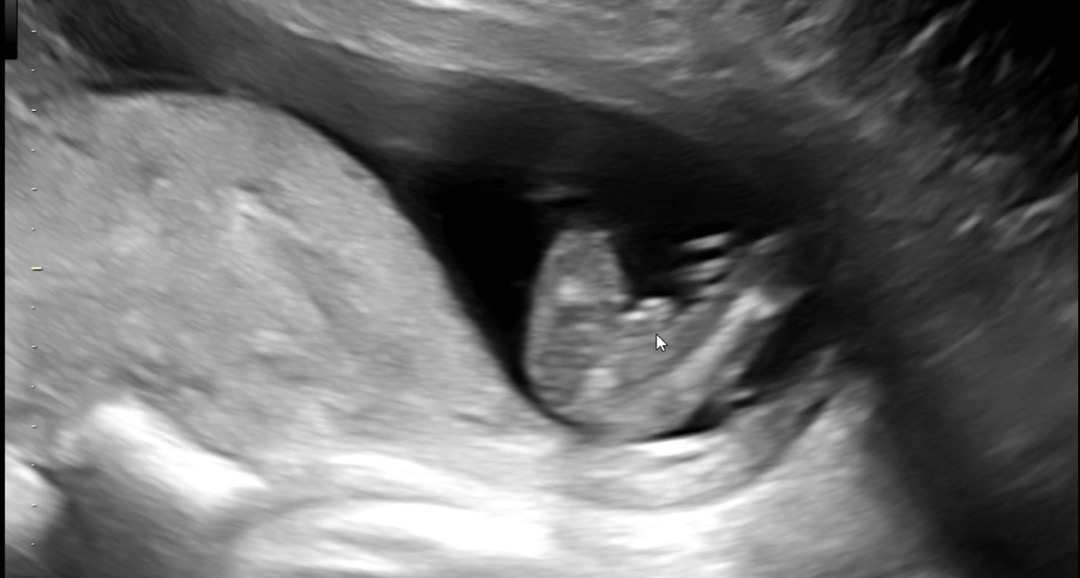

아들이겠죠?..ㅎ

선생님은 아직 애매하다고 다음 입초때 보자고 하시는디....

저도 13주에 저정도 봤는데 16주에 아들확정받앗어요 ㅋㅋㅋ

저희 아들인데 그때쯤에 저렇게보긴했는데 끝부분이 조금 미사일같았는데 담이쌀이님은 동그래서 애매하네욤 ㅠㅠㅎㅎㅎㅎ

첫째도 아들 둘째도 아들품고있는데..; 15주에 저정도 튀어나옴...아들인것같아요

15주 5일이에요